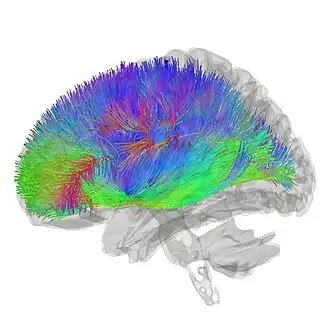

![]() Striatum shown in green with other basal ganglia and thalamus. Small region in yellow is the amygdala | |